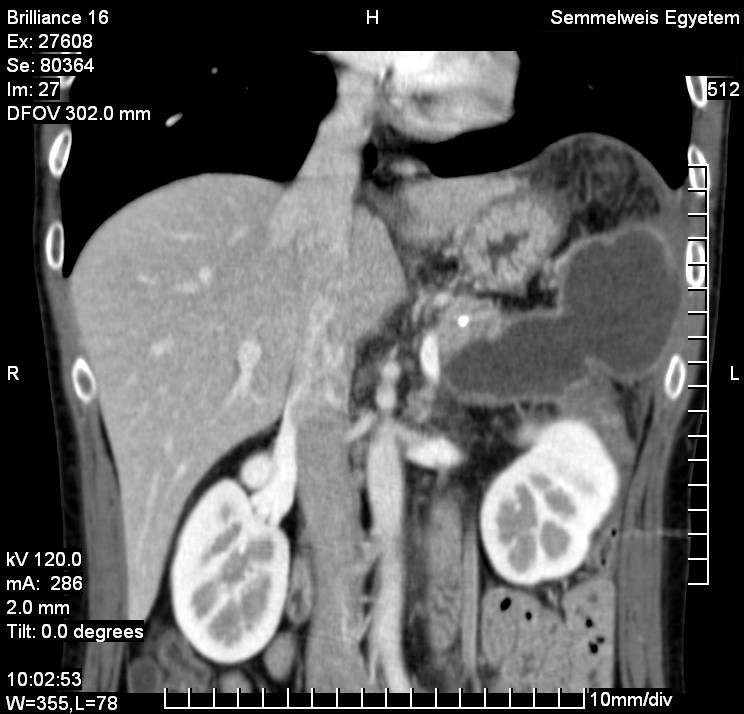

The simple cyst (Figure 16) indicates a difference from the multicystic liver only in the number of the cysts. Conversely, the polycystic liver (Figure 17) is an autosomal dominant inheritant disorder, in which the cystic conversion can be present in up to 70-80% of the liver parenchyma due to the large number of the cysts. It often accompanies with polycystic kidneys, whilst the entire polycystic syndrome – if also polycystic affection of the pancreas is also associated – occurs very rarely.

Figure 17: Polycystic liver, contrast enhanced CT